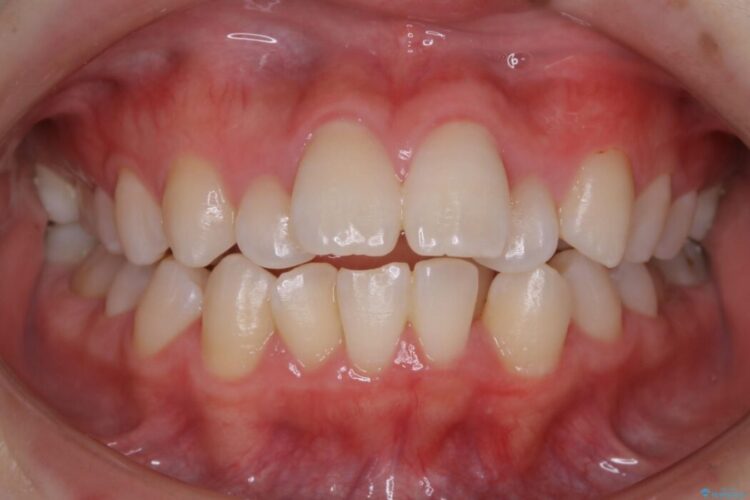

検査したところ歯に対して骨が上顎・下顎共に小さいことがわかりました。

それによりスペースが少なく歯列がガタついたり前方傾斜する生え方となっていました。

本症例の患者様は顎の骨が小さく歯をきれいに並べるための隙間がないため、歯が重なったり傾斜してしまっていました。